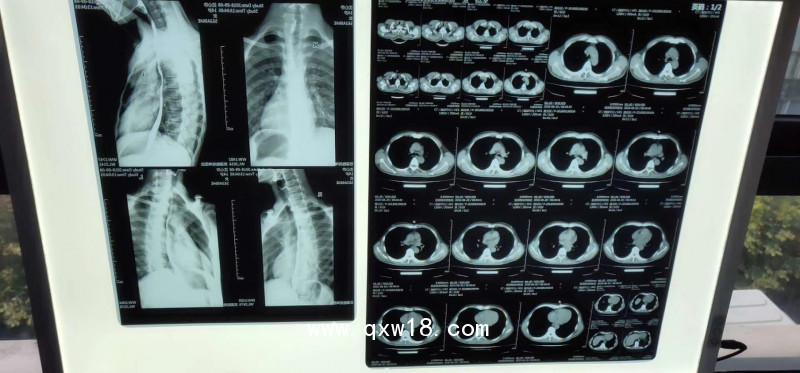

產(chǎn)品名:奧格西熱敏膠片(可提供自助取片機(jī)))